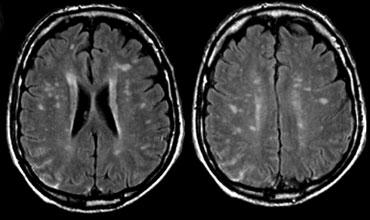

PML liên quan đến Natalizumab. Hình ảnh được cung cấp bởi Bénédicte Quivron CH Jolimont, La Louvière, Bỉ

PML liên quan đến Natalizumab

Bệnh bạch chất đa ổ tiến triển (PML) là bệnh mất myelin do virus JC gây ra ở bệnh nhân suy giảm miễn dịch.

So với các nhóm bệnh nhân PML khác như HIV, các đặc điểm hình ảnh trong PML liên quan đến natalizumab được mô tả là không đồng nhất và biến động.

Các dấu hiệu hình ảnh chính bao gồm:

- Tổn thương khu trú hoặc đa ổ ở chất trắng dưới vỏ trên lều, liên quan đến sợi chữ U và chất xám vỏ não; ít gặp hơn ở hố sau và chất xám sâu

- Tăng tín hiệu T2W (đôi khi có các tổn thương ổ nhỏ ở vùng lân cận tổn thương chính)

- Đồng tín hiệu hoặc giảm tín hiệu T1W tùy theo mức độ mất myelin

- Khoảng 30% bệnh nhân có tổn thương PML ngấm thuốc tương phản từ.

- Tăng tín hiệu trên DWI đặc biệt ở vùng rìa tổn thương, phản ánh tình trạng nhiễm trùng đang hoạt động và phù nề tế bào chất trắng.

- FLAIR có độ nhạy cao nhất trong phát hiện tổn thương PML

- Chuỗi xung T2W có thể hiển thị một số đặc điểm của tổn thương PML (ví dụ: vi nang)

- T1W có và không có thuốc tương phản từ giúp đánh giá mức độ mất myelin và dấu hiệu viêm.

- DWI hữu ích trong phát hiện nhiễm trùng đang hoạt động.